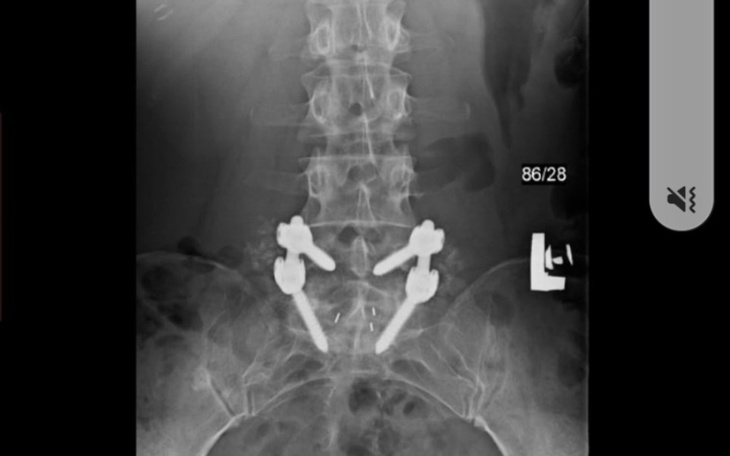

Dzień dobry jestem Małgosia mam 49 lat i jestem osobą skrzywdzona przez los. Poszukuje osób dobrego serca jestem ofiarą przemocy w rodzinie i jestem w bardzo trudnej sytuacji finansowej. Potrzebne sa środki finansowe na kolejną operacje i rehabilitację. Jestem chora na przewlekłą chorobę - Stwardnienie Rozsiane. Na tę chwile leczenie w Polsce nie jest skuteczne. Jestem po bardzo ciężkiej operacji kręgosłupa-stabilizacja tytanowa z odbarczeniem części lędziowej, gdyż podczas operacji okazało się że jeden kręg jest cały rozsypany. W obecnej chwili jest znaczne pogorszenie stanu kręgosłupa i oczekuje na kolejną operacje jeśli w Polsce znajdą się lekarze którzy podejmą się takiej operacji.